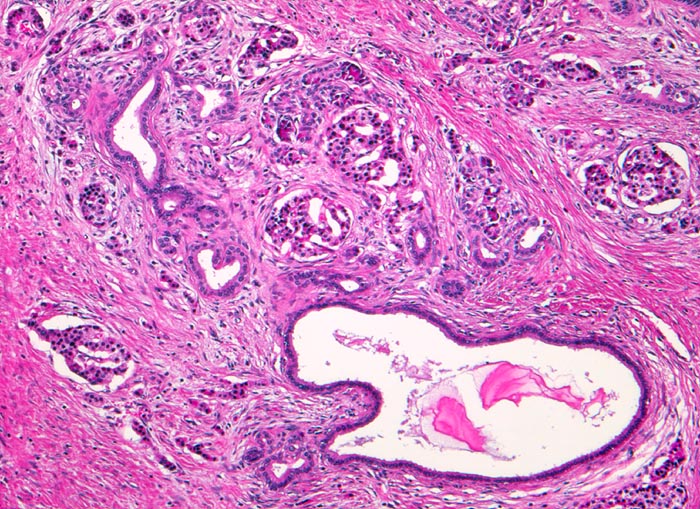

PathoPic – image database / PathoPic ID 4670 - Chronisch-sklerosierende Pankreatitis

Chronisch-sklerosierende Pankreatitis

Die Azini dieses Lobulus sind weitgehend verschwunden. Neben einigen wenigen atrophen Azini sind zahlreiche Inseln des endokrinen Pankreas zurückgeblieben. Stark dilatierter intralobulärer Gang mit retiniertem Sekret. Daneben proliferierte kleinere Gänge. Minimales Entzündungsinfiltrat.

Alkoholiker mit rezidivierten akuten Pankreatitisschüben. Chronische Diarrhoe.

Histologie

100